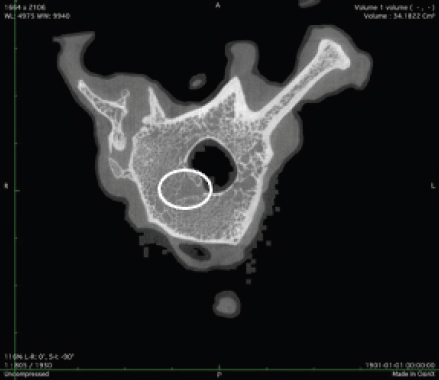

μCT scan

Using X-ray imaging, every volumetric element of the sample, not just its surface contour, was digitized. We obtained almost 24 GB of data, which required specialized software for its analysis. The trabeculae in the vertebral body can be seen clearly in Figure 7. After analyzing the different sections, we discovered that there are locations in the vertebral body where porosity is very high, and it is reasonable to assume that these cavities are filled with connective tissue. The bone tissue in these locations is more fragile; there has been a change in the bone structure, and there would be an increased fracture risk.

Fig. 7. Visible defects in the canine L2 vertebra.